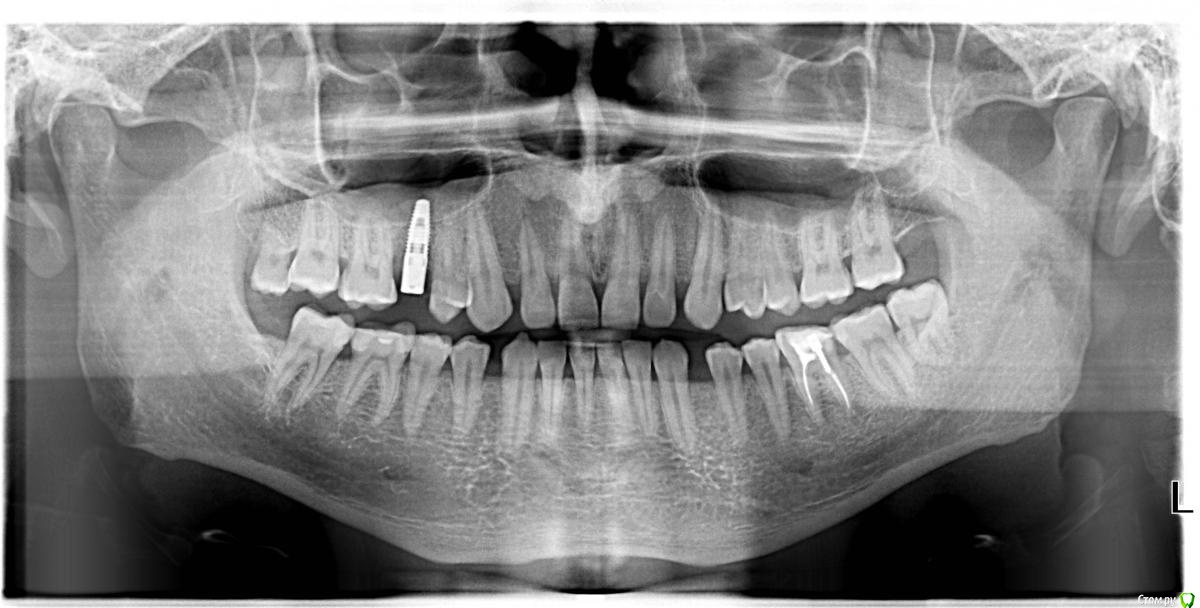

akudja Опубликовано 11 января, 2017 Поделиться Опубликовано 11 января, 2017 (изменено) Доброго времени суток.Интересует другое мнение по ситуации с зубами, есть три ортопантомограммы сделанные в разный промежуток времени:04.04.2014 14.06.2016 11.01.2017 1. Кто либо видит где нибудь кисту по этим снимкам?2. Действительно ли каналы 36го зуба (правый нижний ряд по снимку, 6ой зуб) недопломбирован/ы?3. Наиболее оптимальное решение для указанного в вопросе № 2 зуба - доделка и установка коронки или удаление с последующей имплантацией?4. 18й зуб (левый верхний ряд, последний зуб) есть ли необходимость в его удалении при условии, что он здоров, соседние зубы не трогает и им не мешает, владельцу зуба также никаких неудобств не доставляет? Так как будучи пациентом удостовериться в достоверности диагноза врача нет возможности, остается уповать на его добросовестность, но хотелось бы иметь разностороннюю точку зрения. Заранее благодарю за ответы. Изменено 11 января, 2017 пользователем akudja Ссылка на комментарий

red_butler Опубликовано 12 января, 2017 Поделиться Опубликовано 12 января, 2017 1. Кто либо видит где нибудь кисту по этим снимкам? для постановки данного диагноза требуется гистологическое исследование. 2. Действительно ли каналы 36го зуба (правый нижний ряд по снимку, 6ой зуб) недопломбирован/ы? да 3. Наиболее оптимальное решение для указанного в вопросе № 2 зуба - доделка и установка коронки или удаление с последующей имплантацией? Для ответа нужен очный осмотр 4. 18й зуб (левый верхний ряд, последний зуб) есть ли необходимость в его удалении при условии, что он здоров, соседние зубы не трогает и им не мешает, владельцу зуба также никаких неудобств не доставляет? удаляйте, зуб лишен антагониста, выдвинулся и поражен кариесом. 1 Ссылка на комментарий